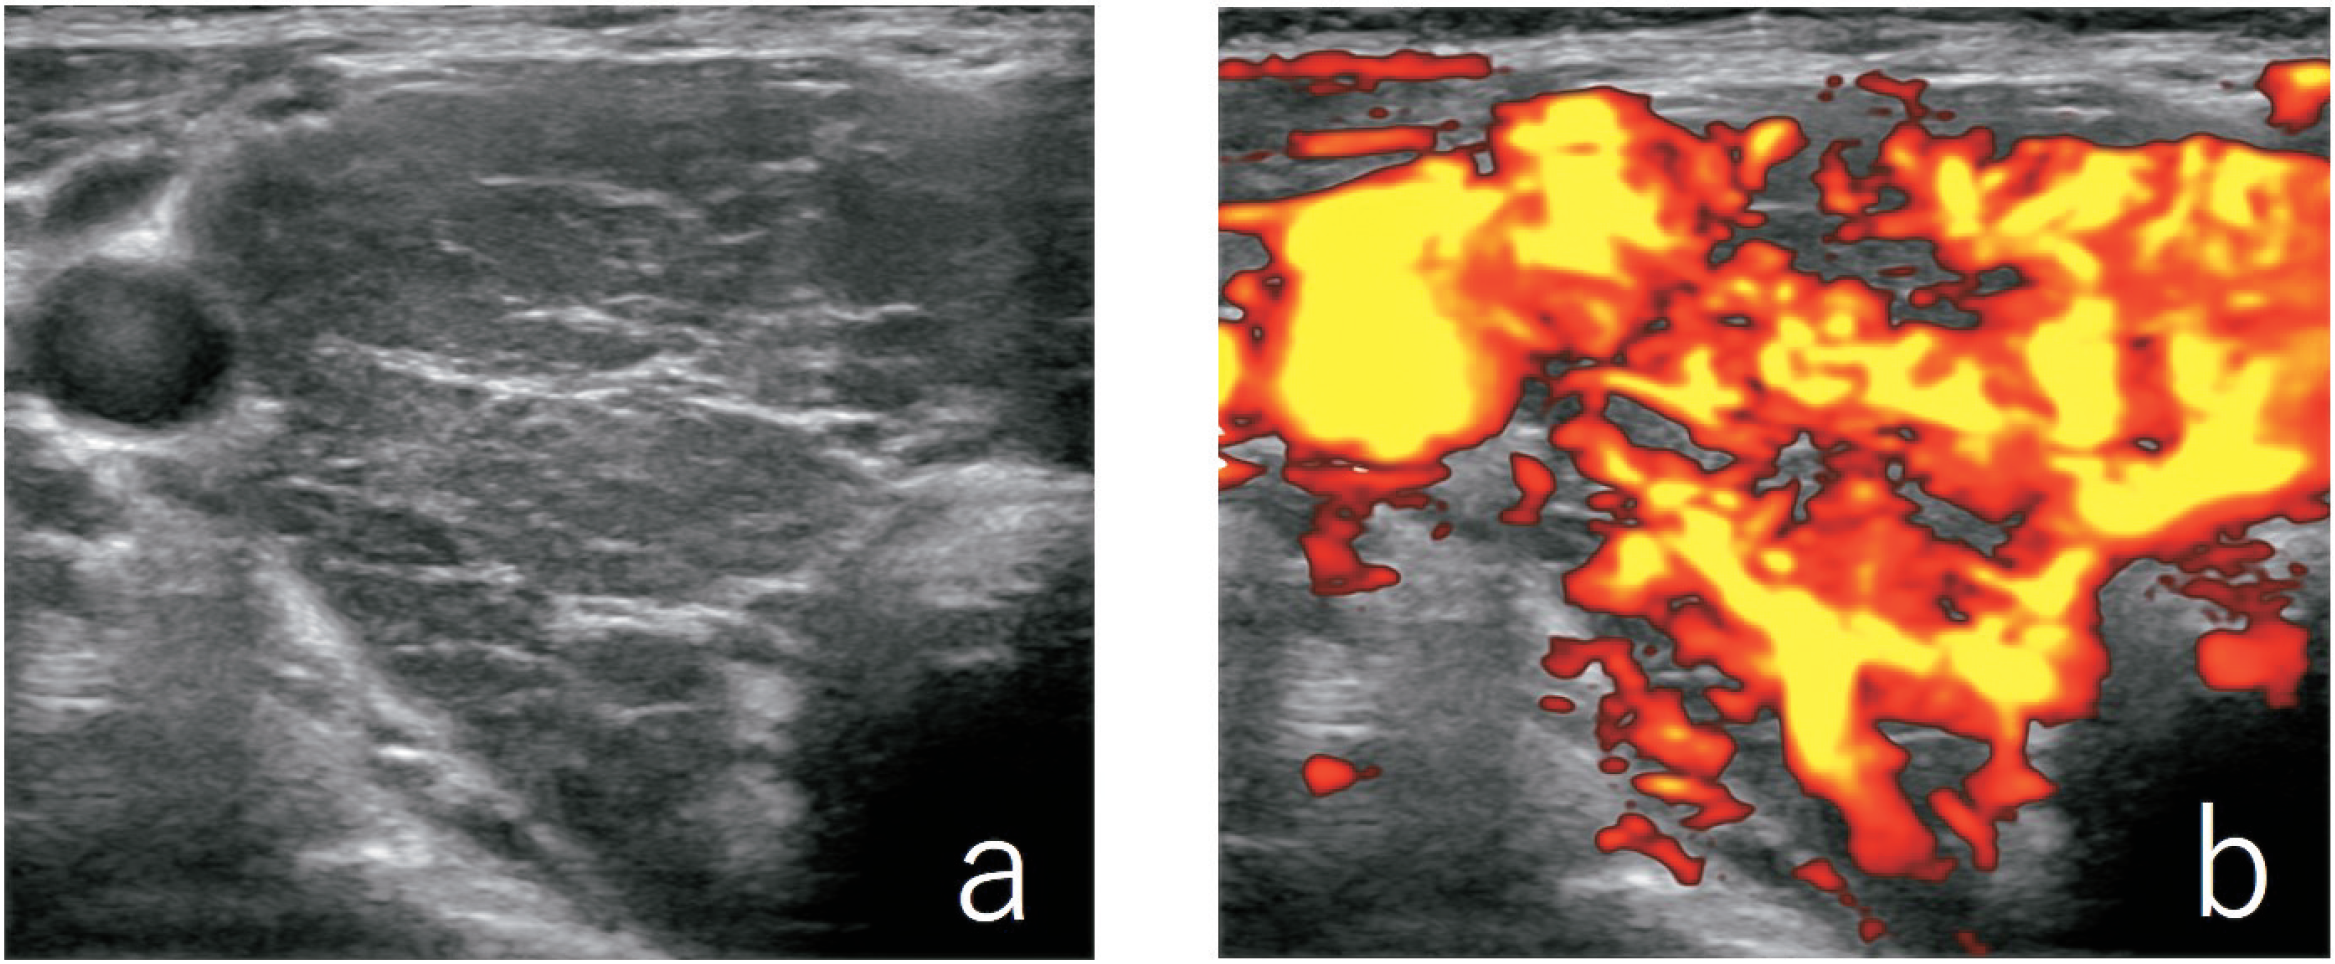

甲状腺右葉の超音波Bモード像(a)及びパワードプラ像(b)を示す。

最も考えられるのはどれか。

1. Basedow病

2. 副甲状腺腫大

3. 亜急性甲状腺炎

4. 腺腫様甲状腺腫

5. 慢性甲状腺炎〈橋本病〉